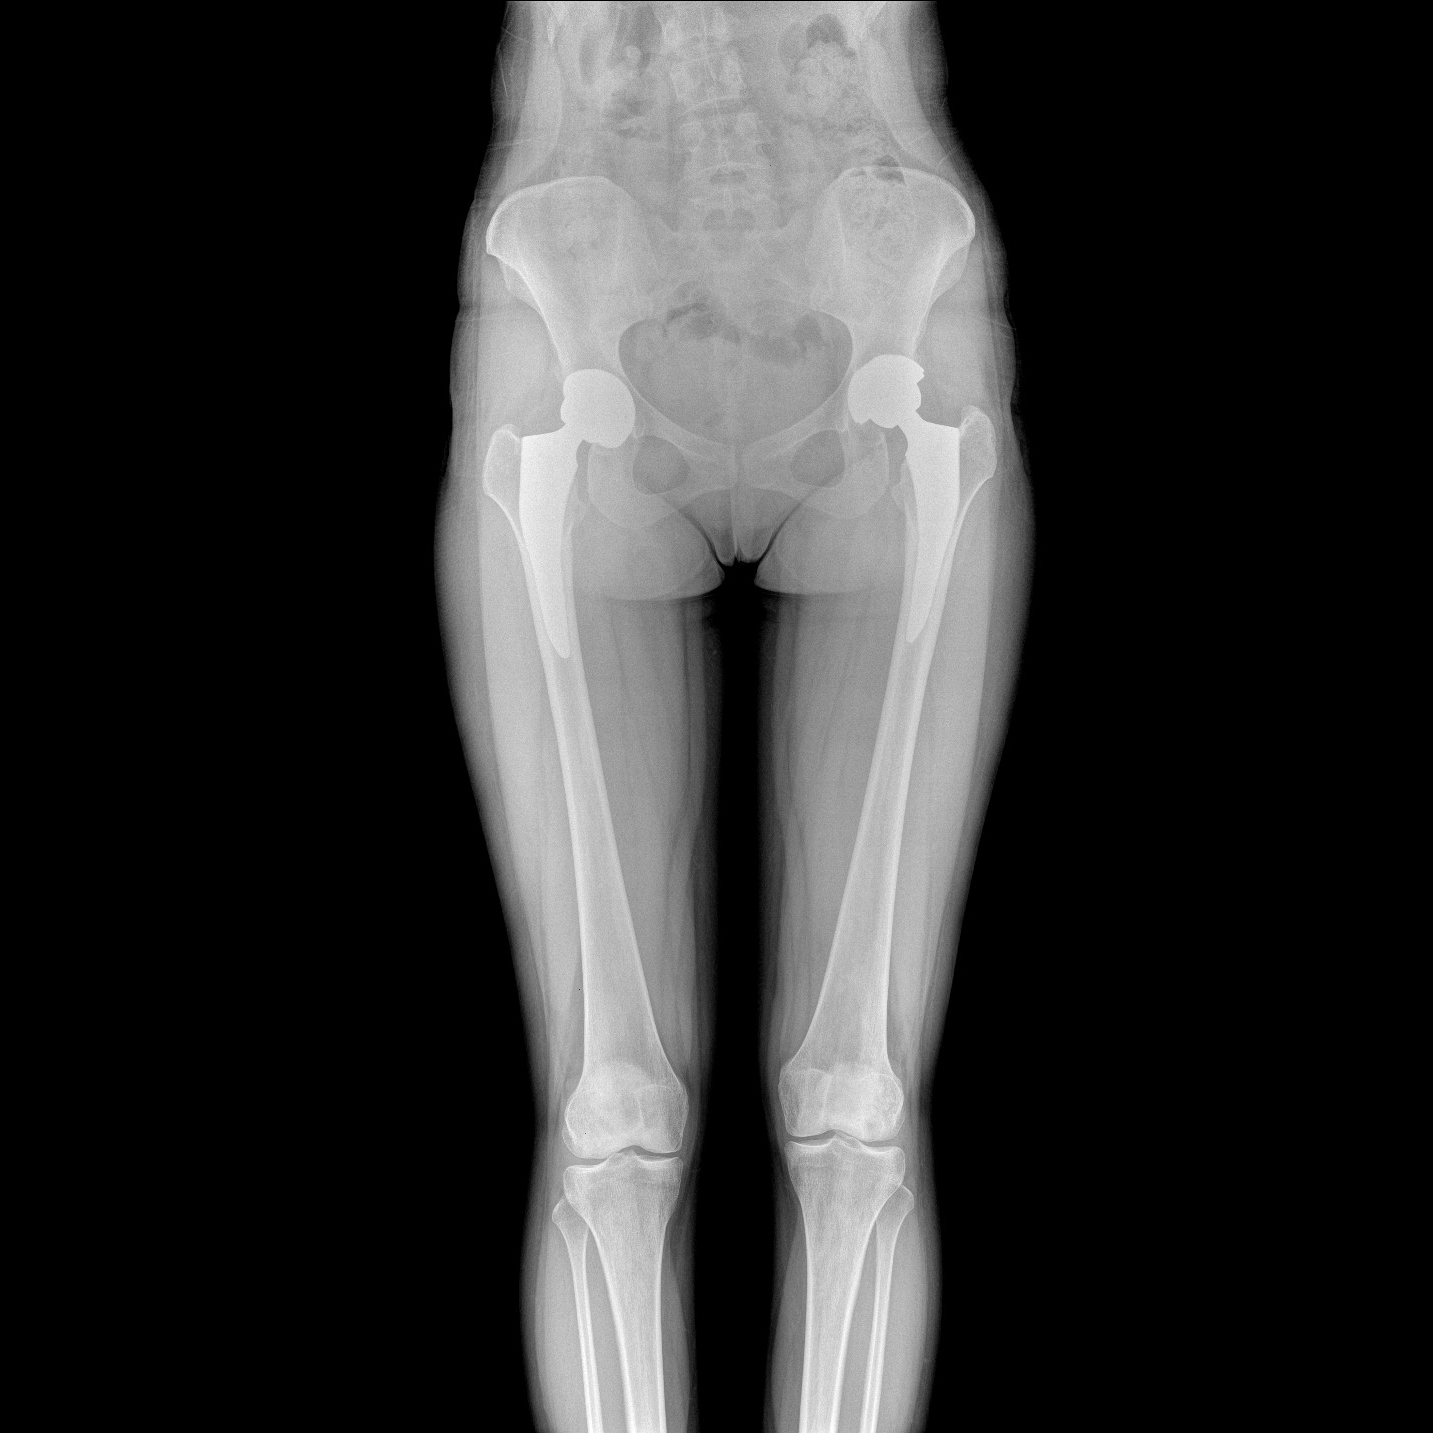

支持全脊柱攝影、雙下肢攝影、脊髓造影、復(fù)雜創(chuàng)傷、人工關(guān)節(jié)置換、關(guān)節(jié)損傷的修復(fù)重建等大視野臨床應(yīng)用

17"*34"有效視野,一次成像不拼接。相較于多張攝影再軟件拼接的DR設(shè)備,PLX8600解決了拼接圖像存在密度不均勻,拼接處圖像配準(zhǔn)和放大效應(yīng)等問(wèn)題,給臨床帶來(lái)了大視野影像解決方案,可一次性覆蓋全脊柱或雙下肢影像。